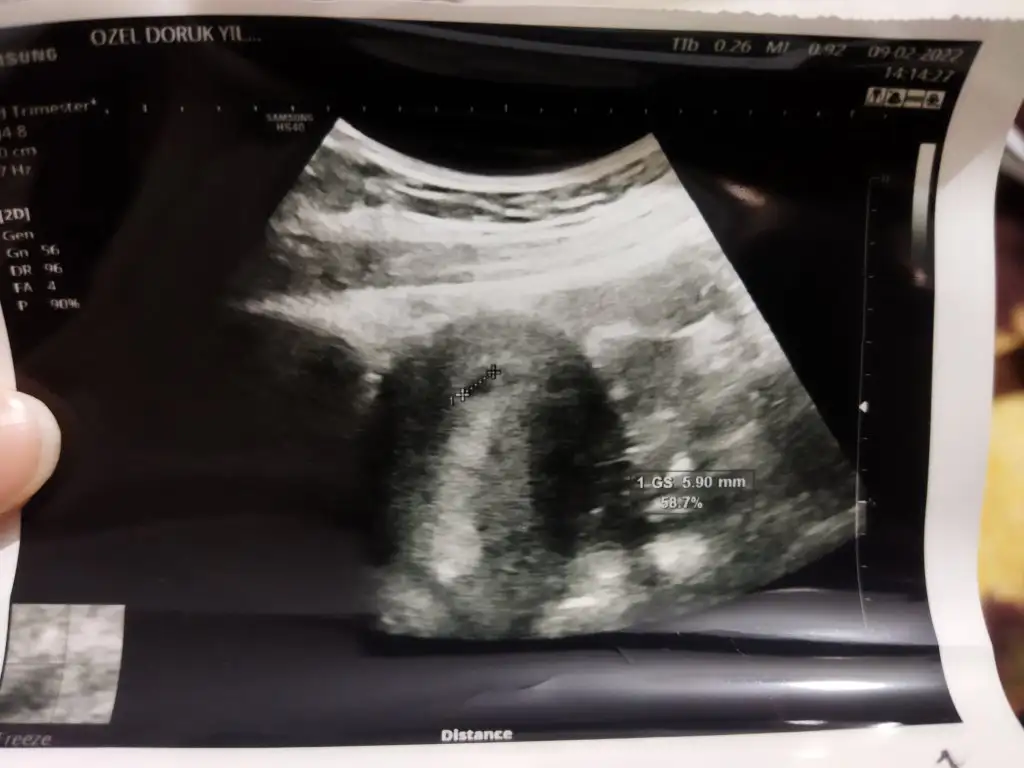

Karından ilki bir aylık diğeri üç yâda iki

Merhaba 8 haftalık karından bakıldı

14,9 KB · Görüntüleme: 74